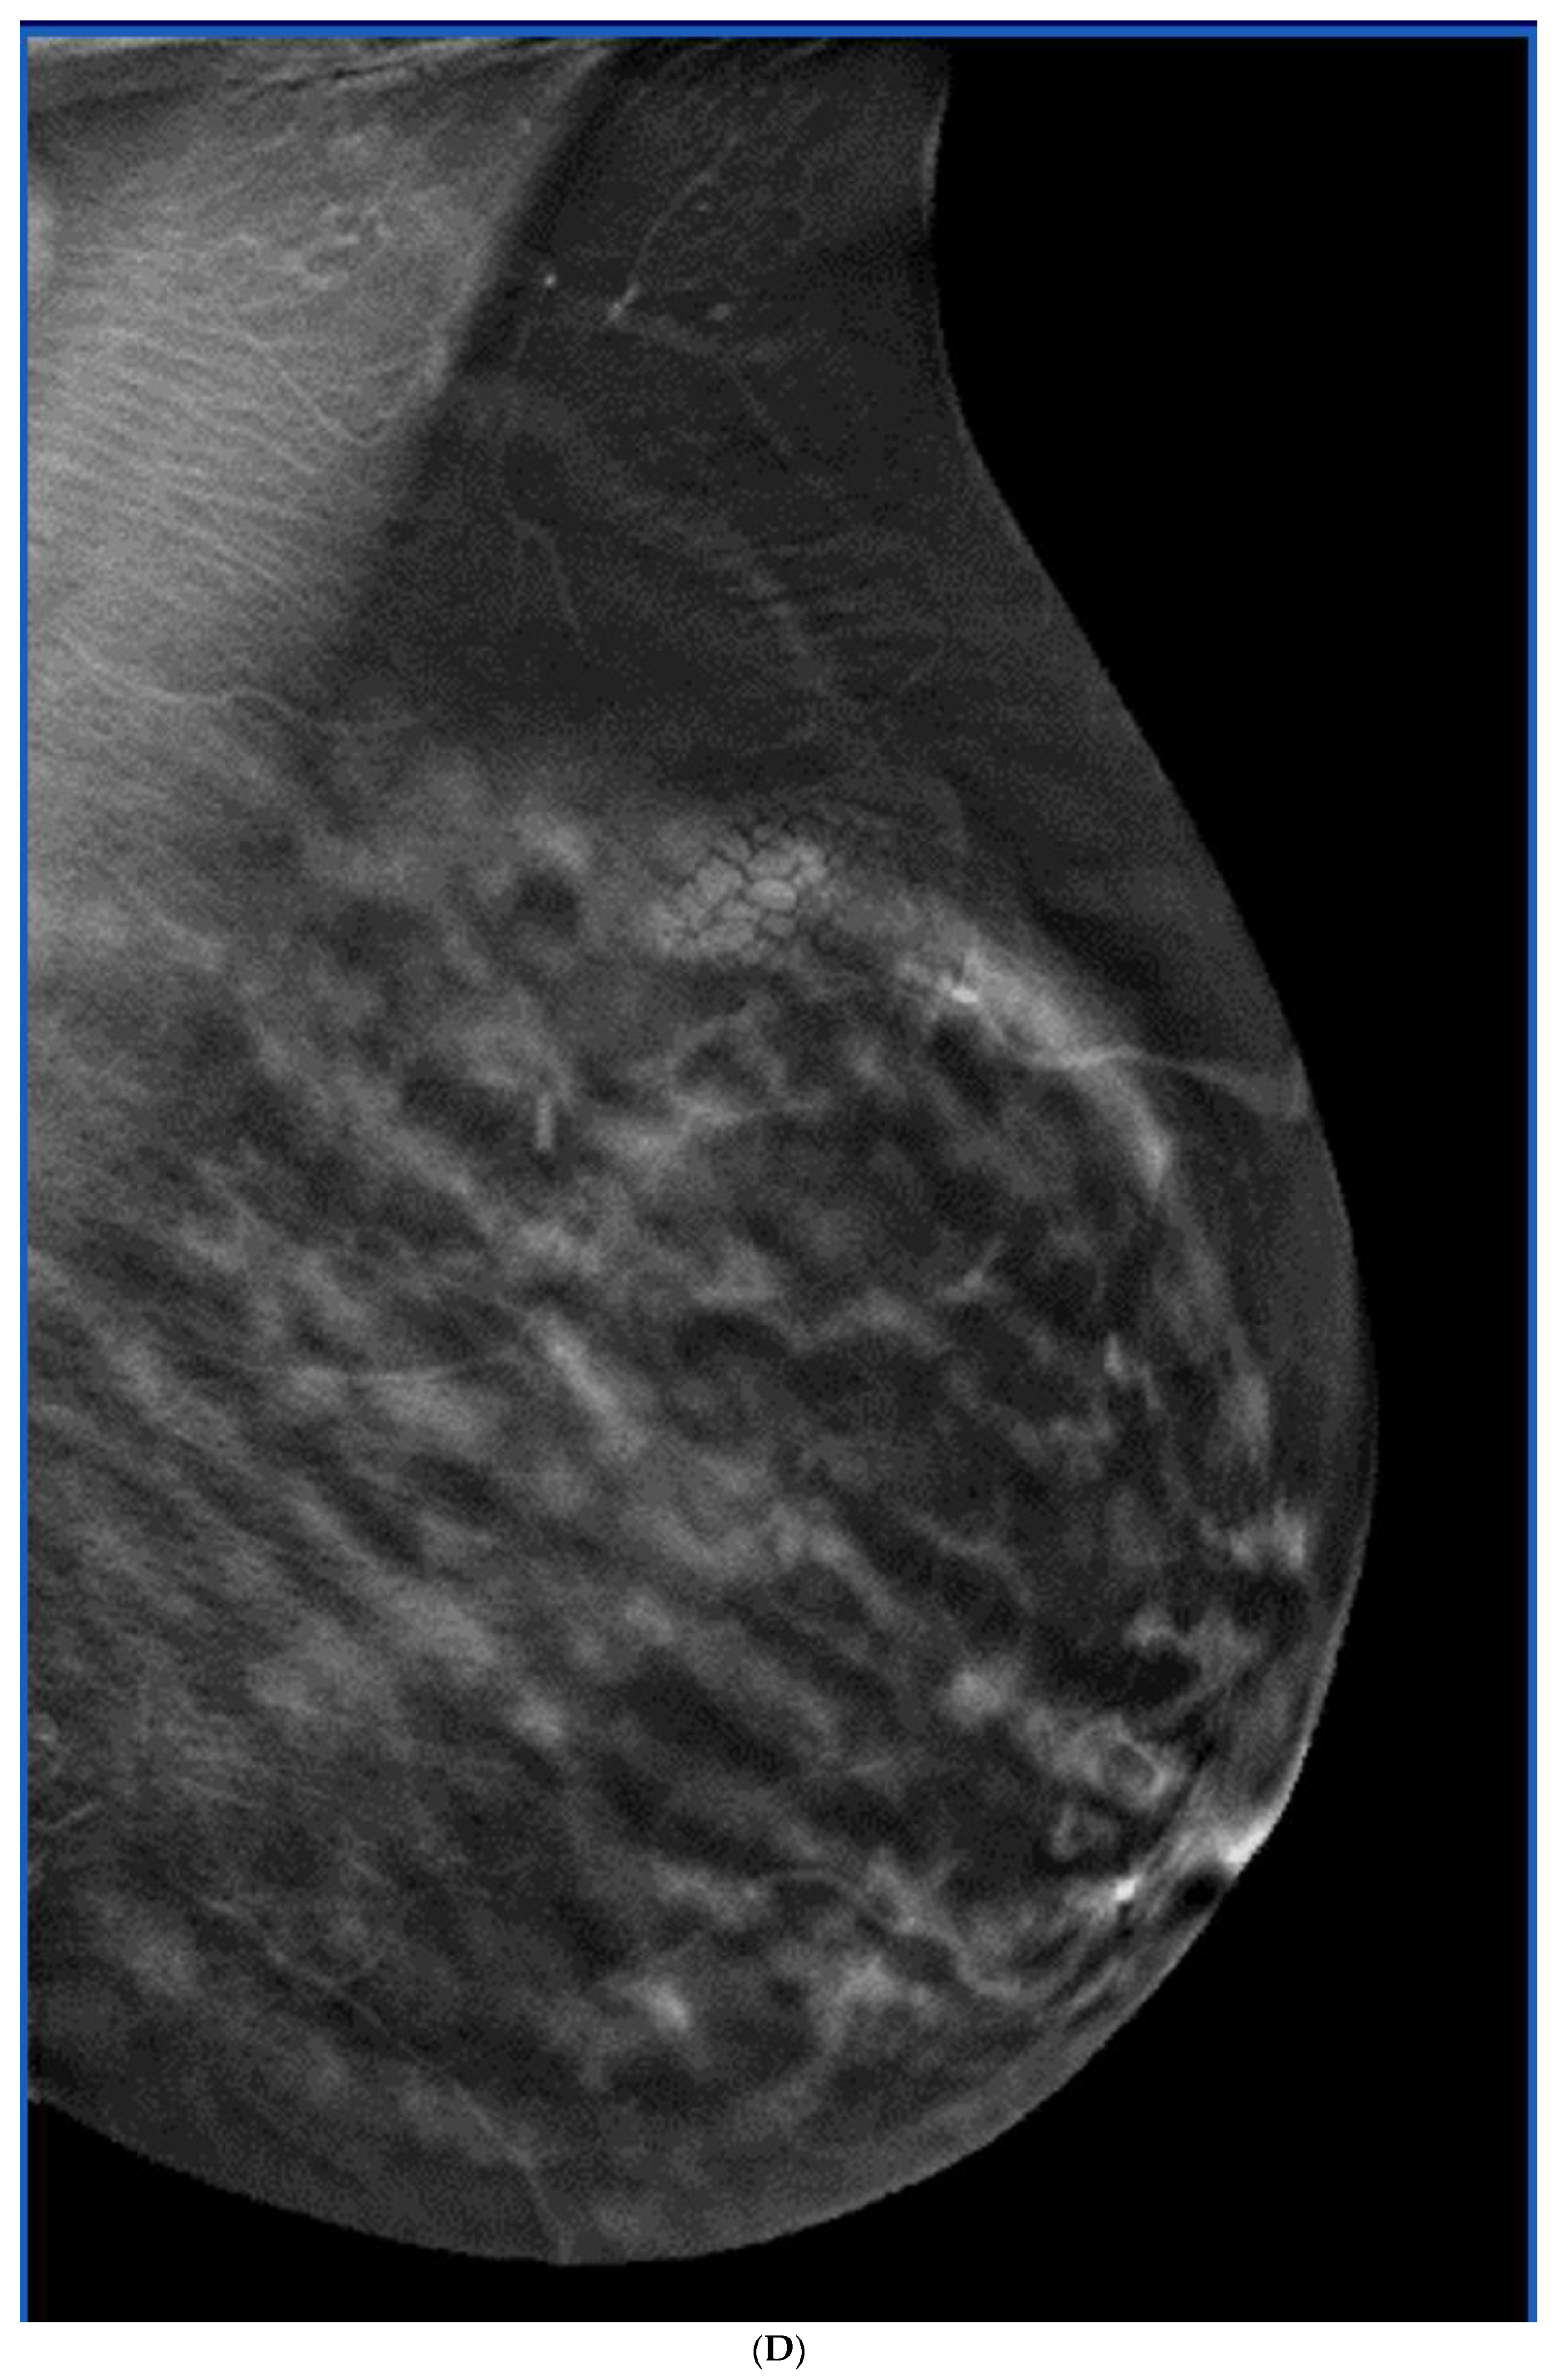

6. Digital Breast Tomosynthesis (DBT)